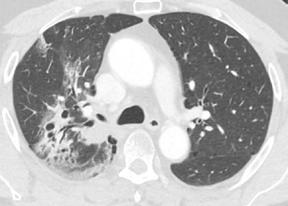

El día 18/2/2022 el paciente refiere dolor torácico. Se realiza un electrocardiograma, que muestra elevación del segmento ST en las derivaciones anteriores en relación con un infarto agudo de miocardio (IAM) anterior. Se activa código infarto y se realiza una coronariografía emergente, que muestra una oclusión de perfil embólico en la arteria descendente anterior media (Figura 1, flecha amarilla). Se trata con trombectomía aspirativa con buen resultado angiográfico final con flujo TIMI 3. Se inicia tratamiento con perfusión de heparina sódica. El día 19/2 el paciente comienza con cefalea muy intensa y afasia, por lo que se activa nuevamente código ictus y se realiza un angioTAC craneal que muestra una hemorragia subaracnoidea (HSA) de predominio izquierdo secundaria a sangrado por un aneurisma disecante de la rama M2 de la arteria cerebral media izquierda (Figura 2, flecha amarilla). Se decide completar estudio con una angiografía que confirma los hallazgos del TAC. Por el alto riesgo de resangrado y la necesidad de anticoagulación oral permanente, se decide embolización del aneurisma con coils, que resulta exitoso (Figura 3, flecha amarilla). Se reinicia durante el ingreso perfusión de heparina sódica y unos días antes del alta se comienza con anticoagulación oral con apixaban 5 mg/12 horas. La evolución clínica es favorable, siendo la exploración física al alta normal. Tras tres años de seguimiento bajo tratamiento con apixaban 5 mg/12 horas no han sido reportados nuevos episodios de sangrado ni de trombosis.

Figuras 1 y 2: Prótesis aórtica migrada y disección aórtica focal tipo A, de origen en la curvatura menor del arco aórtico (zona 0) hasta la bifurcación de la arteria braquiocefálica derecha; sin afectación de del resto de troncos supra-aórticos, del resto del cayado aórtico o de la aorta descendente.